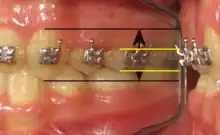

- 2. Stimulera les mécanorécepteurs périodontaux lors de l'intercuspidation maximale (Fig. 18) des 1500 à 2000 déglutition salivaire quotidiennes (« occlusion réflexe » et déglutition physiologique « en dents serrées ») ;

- Dès le plus jeune âge (enfant, adolescent), mise en place d'un réducteur d'espace interocclusal de repos, ou REIOR[45], sur les molaires supérieures (Fig.13), gauche et droite : deux molaires lactéales (4 à 8 ans) ou deux molaires permanentes (à partir de 10 ans).

- Suivant l'Espace libre phonétique, l'épaisseur du REIOR varie de 3 à 6 millimètres. Au-delà de ces dimensions, il faut s'attendre à des fractures de cisaillement du matériau ou à un décollement du composite.

- L'intercuspidation sur un REIOR suit les mêmes règles que la fermeture occlusale sur un plan de morsure rétro-incisif (occlusodontologie[6]) : décontraction innée de tous les muscles manducateurs et manipulation extrêmement douce par la main de l'opérateur sous la mâchoire de l'enfant ou de l'adolescent.